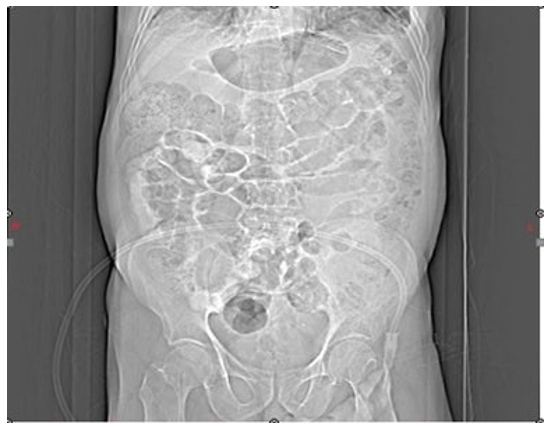

The patient was treated for COPD exacerbation and pneumonia, resulting in a decrease in cough and phlegm; however, the chest pain persisted. During daily evaluations, an increase in troponin levels was noted, prompting a cardiology consultation. The consultation recommended initiating anticoagulation therapy to achieve an INR of 2-3 and performing coronary angiography once the patient's pulmonary status stabilized. After starting anticoagulants (heparin and warfarin), the patient developed abdominal pain in the periumbilical region that radiated to the back. The patient did not exhibit any signs of external hemorrhage, such as melena, hematemesis, rectorrhagia, hematuria, or hemoptysis, and an ultrasound of the abdomen and pelvis was normal. However, due to the persistence of pain and a 3 g/dL drop in hemoglobin, a CT scan with oral and IV contrast of the abdomen and pelvis was requested, which revealed a 110 x 180 mm retroperitoneal hematoma (Figure 3 and 4).

Figure 4: Abdominal Distension